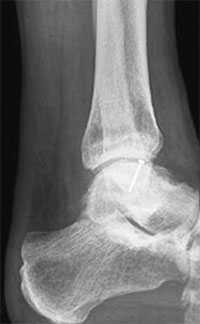

Не смотря на то, что Loomer с соавт. сообщили, что только от 50% до 66% остеохондральных дефектов обнаруживаются при помощи обычной рентгенографии, данный метод является важной отправной точкой и может быть полезен для исключения другой патологии голеностопного сустава [20]. Рентгенологическое исследование голеностопного сустава должно включать переднюю, заднюю и в 3⁄4 внутренней ротации проекции. Все проекции выполняются стоя (под нагрузкой) и называются функциональными. Функциональные рентгенограммы могут быть полезны для выявления сопутствующей нестабильности голеностопного сустава, проекция 3⁄4 во внутренней ротации, помогает в визуализации щели межберцового синдесмоза, а так же отображает передне-внутрений импижмент (таранной и большеберцовой кости) в случае его наличия. Выполненные в положении подошвенного сгибания прямая и 3⁄4 проекция во внутренней ротации могут быть полезны в выявлении заднемедиального поражения таранной кости. Рентгенологические признаки, которые могут быть определены, варьируются от небольших участков сдавления субхондральной кости до крупных отслоенных остеохондральных фрагментов. Радиографическая

система классификации была разработана Berndt и Harty в 1959 году и остается золотым стандартом. (Табл. 1) [16]. Loomer с соавторами дополнили имеющуюся классификацию, на основе не только рентгенограмм, а также МРТ (магнитно-резонансная томография) и КТ (компьютерная томография), и добавили стадию V в систему классификации Berndt и Harty [22].

МРТ является ценным инструментом в комплексе диагностики ОХПТК для оценки отека костной ткани, а также выявления скрытых повреждений субхондральной кости и хрящевого покрытия, которые могут быть пропущены при стандартных рентгенограммах или даже КТ. МРТ – самый лучший инструмент оценки для определения стабильности и жизнеспособности фрагмента таранной кости при его отслоении и эта информация может быть решающей в тактике выбора того или иного метода хирургического лечения. Однако, для определения размеров отслоившегося фрагмента таранной кости наилучший метод КТ, так как данные размеров по МРТ могут не соответствовать действительности в сторону переоценки последних. Hepple с соавторами изучив многочисленные данные МРТ диагностики разработали систему классификации ОХПТК на основе этого метода (Табл. 2) [23]. Однако, наиболее широко принятая система классификации, основанная на КТ-это классификация Ferkel и Sgalione (Табл. 3; Рисунок 4) [24]. Классифицировать ОХПТК также возможно выполнить интраоперационно, на основе артроскопических данных о состоянии остеохондрального поражения. Наиболее широко используется система Ferkel/Cheng (Табл. 4) [25], эта система классификации, в отличие от обычных рентгенограмм, КТ и МРТ, лучше всего взаимосвязана с исходами лечения пациентов.

Рентгенография

Рутинное рентгенологическое исследование включает рентгенографию обоих голеностопных суставов в прямой и боковой проекциях. На рентгенограммах можно увидеть отслоенный костный фрагмент. Изначально, на начальных стадиях болезни, площадь повреждения может быть очень мала, в связи с чем она не будет видна на рентгенограммах. Иногда изменения становятся видны только при рентгенологическом исследовании в динамике.